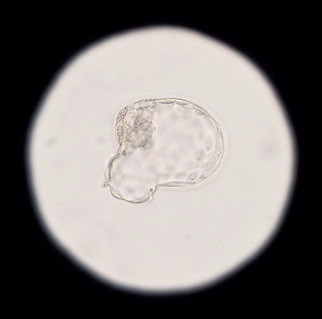

Скорее всего, потребуется ИКСИ, ICSI (Intracytoplasmic sperm injection) — инъекция сперматозоида в цитоплазму яйцеклетки. Эта технология чаще всего применяется при мужском бесплодии. Эмбриолог с помощью электронного микроскопа отбирает лучшие сперматозоиды, а затем супертонкой иглой вводит их в ооциты (в одну яйцеклетку — один сперматозоид).